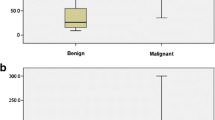

There were 310 benign lesions and 204 malignant lesions included in this study. Lesion size ranged from 4 to 72 mm, and the median size was 13 mm. Table 2 summarizes the demographic information for all participants. The corresponding quantitative parameters from SWE and HDMI are also presented. Stiffness (Emax and Emean) values were significantly higher for malignant lesions than for benign lesions. Vessel diameter (Dmax, Dmean) and number of vessel segments (NV) were significantly larger for malignant lesions than for benign lesions. Also, malignant lesions showed significant abnormalities in microvessel morphological parameters, such as mvFD [30], NB, VD, τmax, τmean, MDmax, MDmean, BAmax, and BAmean, highlighting the importance of structural complexity and irregularity of tumor microvessels in addition to increased vessel density.

The models developed using parameters from HDMI only and from SWE only were denoted as “HDMI model” and “SWE model,” respectively. The corresponding ROC curves are shown in Fig. 4a. NV, NB, VD, SVP, Dmax, Dmin, τmean, τmax, BAmean, BAmax, MDmean, and FD were included in the HDMI model. The AUC was 0.912 (95% CI 0.87–0.96). With an optimal cutoff for the malignancy probability at 0.25, the sensitivity and specificity were 82.1% (0.70–0.90) and 85.1% (0.75–0.91), respectively. Emean, Emax, and fmass were included in the SWE. The AUC was 0.888 (95% CI 0.83–0.95). With an optimal cutoff for malignancy probability at 0.28, the sensitivity and specificity were 85.1% (0.74–0.92) and 92.0% (0.84–0.96), respectively.

HDMI parameters were first combined with the SWE parameters, and the model was denoted as the HDMI-SWE model. NV, NB, VD, SVP, Dmax, Dmin, τmean, τmax, BAmean, BAmax, MDmean, FD, Emean, Emax, and fmass were included in the HDMI-SWE model. The AUC (0.973, 95% CI 0.95–0.99) was significantly improved when compared to the HDMI model (p = 0.001) or the SWE model (p = 0.004). With an optimal cutoff for the malignancy probability as 0.25, the sensitivity and specificity were 95.5% (0.87–0.99) and 89.7% (0.81–0.95), respectively.